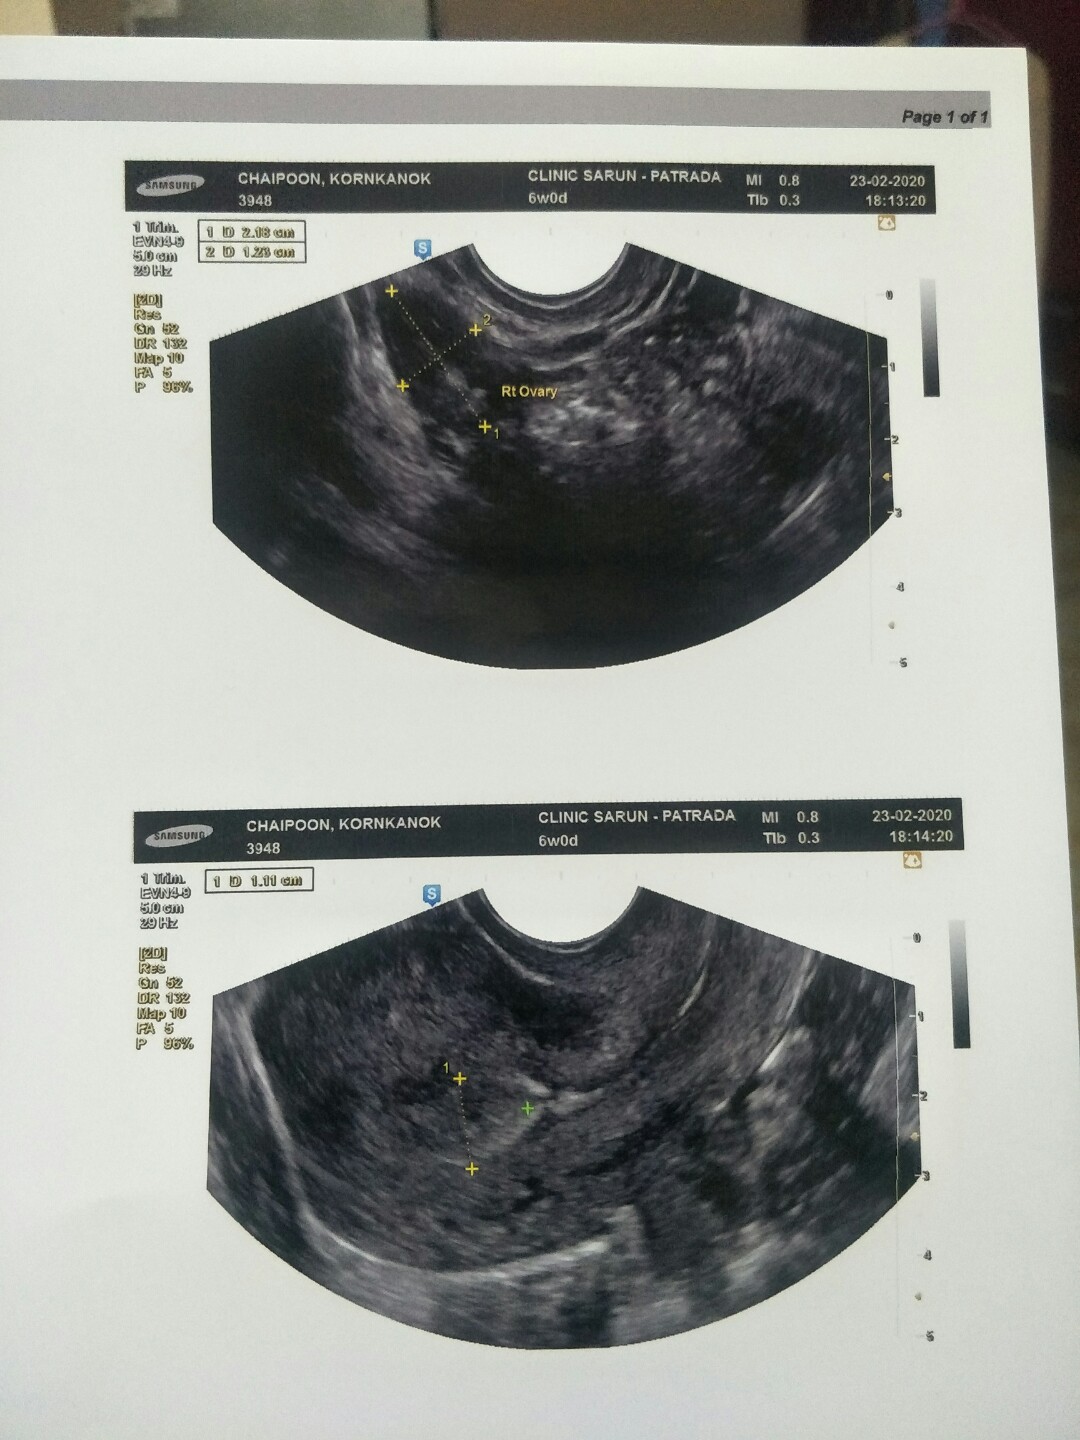

ยุคลีนิค8สัปดาห์กำลังซาวด์เลยค่ะลุ้นอยู่เหมือนกันเพราะรอบแรก6สัปดาห์ไม่เจอลุ้นๆจ้า

ถ้าอายุครรภ์น้อยมากๆ ซาวด์จะยังไม่เจอนะคะ สัก 6 สัปดาห์ ซาวด์ผ่านช่องคลอดอาจจะเจอค่ะ